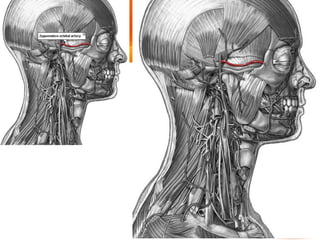

• Se origina en la arteria carótida

común.

• En el niño, es algo más pequeña que

la carótida interna, pero, en el adulto,

los dos vasos son de

aproximadamente el mismo tamaño.

ARTERIA CAROTIDA EXTERNA • Se origina en la arteria carótida común. • En el niño, es algo más pequeña que la carótida interna, pero, en el adulto, los dos vasos son de aproximadamente el mismo tamaño.